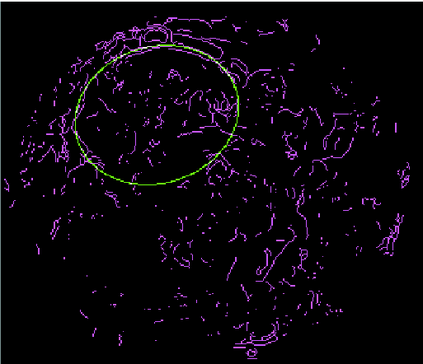

We present a novel method for identification of the boundary of embryonic cells (blastomeres) in Hoffman Modulation Contrast (HMC) microscopic images that are taken between day one to day three. Identification of boundaries of blastomeres is a challenging task, especially in the cases containing four or more cells. This is because these cells are bundled up tightly inside an embryo's membrane and any 2D image projection of such 3D embryo includes cell overlaps, occlusions, and projection ambiguities. Moreover, human embryos include fragmentation, which does not conform to any specific patterns or shape. Here we developed a model-based iterative approach, in which blastomeres are modeled as ellipses that conform to the local image features, such as edges and normals. In an iterative process, each image feature contributes only to one candidate and is removed upon being associated to a model candidate. We have tested the proposed algorithm on an image dataset comprising of 468 human embryos obtained from different sources. An overall Precision, Sensitivity and Overall Quality (OQ) of 92%, 88% and 83% are achieved.